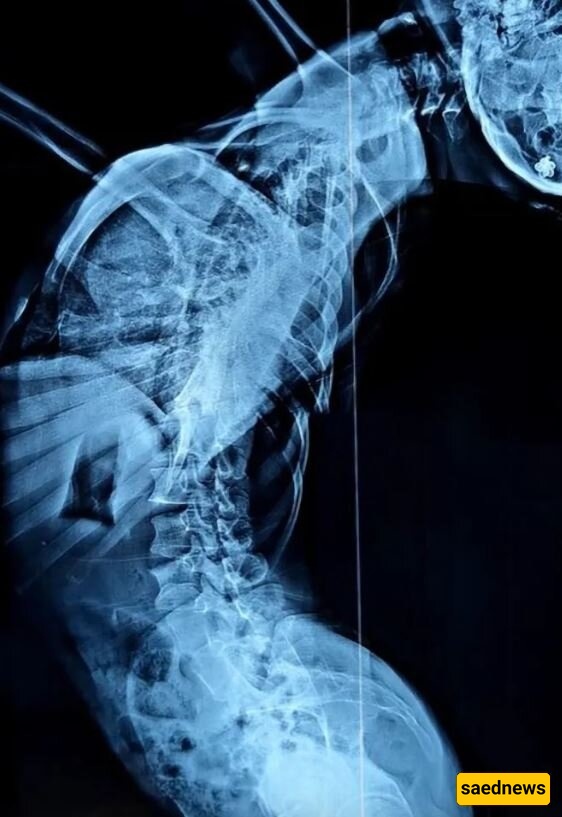

تم تشخیص المرأه البالغه من العمر 37 عامًا بـ الجنف، وهو اضطراب ینحنی فیه العمود الفقری أو یلتف جانبیًا.

کانت المرأه تعانی بشده عند المشی، وکان رأسها یقترب من خصرها—مما یعنی أنه عند الوقوف، کان طولها لا یتجاوز 1.2 متر، وهی مریضه غیر محدده الهویه من مقاطعه قویتشو، الصین.

تُظهر لقطات الفیدیو جسدها على شکل حرف Z منحنی بزاویه 180 درجه إلى الخلف وإلى الیمین. وفی فیدیو آخر، رغم حالتها المتدهوره، تظهر وهی تحاول اصطحاب أطفالها إلى المدرسه.

بلغ طول المرأه بعد العملیه 1.6 متر—أی زیاده قدرها 43 سنتیمترًا، وأجریت الجراحه بواسطه وانغ یو، رئیس جراحی العظام فی مستشفى جامعه بکین.